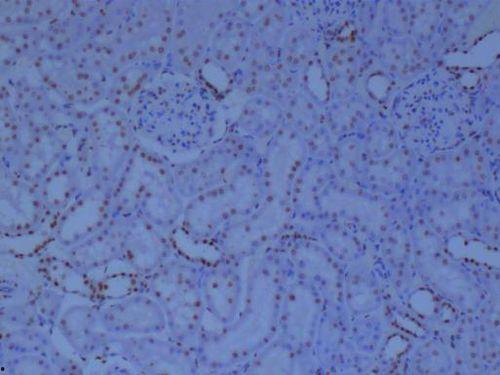

在这段视频中,我们可以看到,实验者首先将组织切片固定在载玻片上,然后依次进行抗原修复、封闭、加一抗、二抗、DAB显色等步骤。每一个步骤都至关重要,缺一不可。通过视频,我们不仅能了解到每个步骤的具体操作,还能看到显微镜下细胞内部的细微变化。

免疫组化技术在疾病研究中发挥着重要作用。在这段视频中,实验者展示了如何利用免疫组化技术检测肿瘤细胞、炎症细胞等。通过视频,我们不仅能了解到免疫组化在疾病研究中的应用,还能看到实验者如何从组织切片中提取有价值的信息。